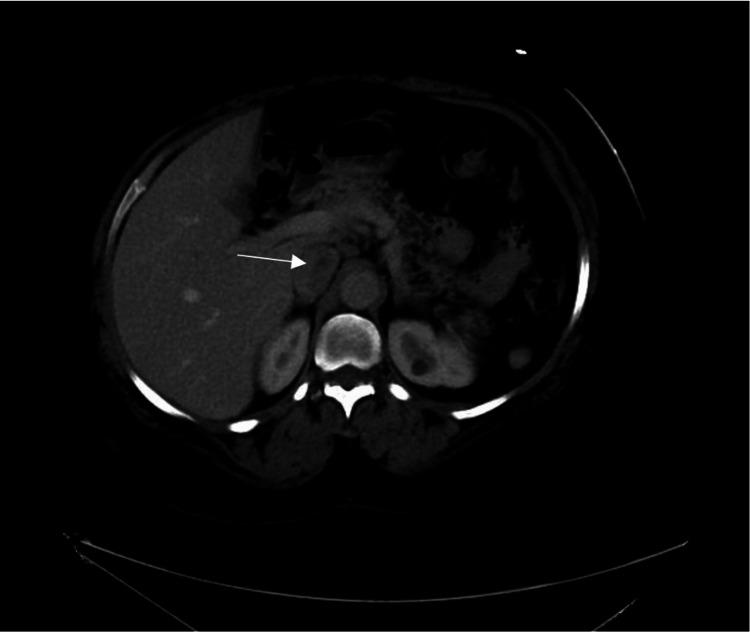

We present a case of a 57-year-old female admitted for non-ST elevation myocardial infarction (NSTEMI), who was incidentally found to have a suspected inferior vena cava (IVC) thrombus. Transthoracic echocardiogram (TTE) demonstrated a right atrial lesion with suspected IVC involvement. Echocardiography incidentally reported a mass extending to the right atrium, and CT imaging reported possible IVC thrombus involvement. Abdominal ultrasound confirmed a suprarenal IVC thrombus. Interventional radiology (IR) performed mechanical thrombectomy and catheter-directed thrombolysis, which was complicated by a stuck catheter and unexpected retrieval of a vascular lesion. Histopathological analysis revealed the lesion to be an arteriovenous hemangioma (AVH). This case underscores the importance of considering rare vascular anomalies, such as AVH, in the differential diagnosis of IVC thrombus and highlights the diagnostic and procedural challenges in managing venous thromboembolism complicated by underlying vascular malformations.

我们报告一例57岁女性因非ST段抬高型心肌梗死(NSTEMI)入院,偶然发现疑似下腔静脉(IVC)血栓形成。经胸超声心动图(TTE)显示右心房病变,疑似累及IVC。超声心动图偶然报告有一肿块延伸至右心房,CT成像报告可能累及IVC血栓。腹部超声证实肾上腺水平的IVC血栓形成。介入放射学(IR)进行了机械血栓切除术和导管定向溶栓治疗,但出现了导管卡顿以及意外取出血管病变的并发症。组织病理学分析显示该病变为动静脉血管瘤(AVH)。该病例强调了在IVC血栓的鉴别诊断中考虑罕见血管异常(如AVH)的重要性,并突出了处理合并潜在血管畸形的静脉血栓栓塞症时的诊断和操作挑战。